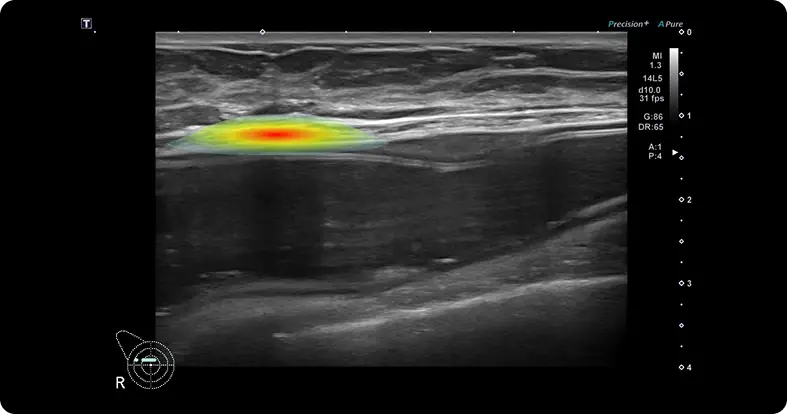

Precise Breast-Implant Diagnosis with ROI MarkingPrecise Breast-Implant Diagnosis with ROI Marking W Expert’s advanced segmentation algorithm highlights the region of interest (ROI) in each ultrasound frame. Through architecture refinements, optimized preprocessing, and fine-tuning, it achieves precise pixel-level delineation, giving surgeons and radiologists clear visual guidance for early detection, objective measurement, and efficient treatment planning.

AI Algorithms for Accurate DiagnosisFine-tuned on over 2.3 million breast-implant ultrasound images, our deep-learning engine delivers clinically proven performance with > 95 % accuracy and > 97 % specificity for key complications such as rupture and capsular change. This validated binary classification provides fast, reproducible results that help clinicians make confident, evidence-based decisions.